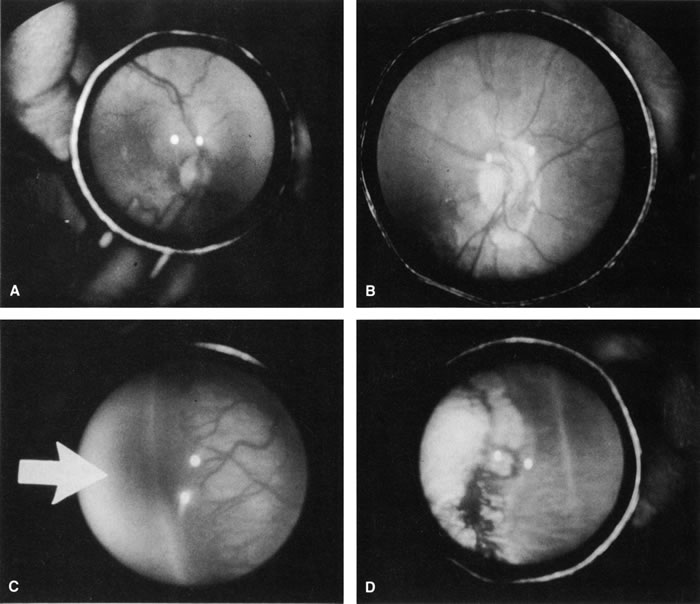

Fig. 4. Preoperative (A) and postoperative (B) appearance of the posterior pole of an infant treated for threshold ROP with cryotherapy. Note the regression of plus disease after treatment. Preoperative (C) and postoperative (D) appearance of the retinal periphery of the same infant. Avascular zone (arrow). Note the regression of the extraretinal fibrovascular proliferation and the cryotherapy scarring.

The desired outcome after cryotherapy is regression of both plus disease and extraretinal fibrovascular proliferation (Fig. 4). Without regression, features of unfavorable outcome, both anatomic and functional, may develop. The structural and functional benefits of cryotherapy in eyes with threshold disease have been demonstrated by the CryoROP study at 1 year, 3 ½, and 5 ½ years post enrollment.11,19 At 10 years post enrollment structural outcome was unfavorable in 47.9% of control eyes versus 27.2% of treated eyes. Unfavorable functional outcome (Snellen visual acuity of 20/200 or worse) was identified in 62.1% of control eyes versus 44.4% of treated eyes at 10 years. The percentage of eyes with 20/40 or better visual acuity was similar for both treated (25.2%) and untreated (23.7%) eyes at 10 years with no statistical difference between the two groups.10

A reduction in both plus disease and extraretinal fibrovascular proliferation should be seen by 1 week after treatment.